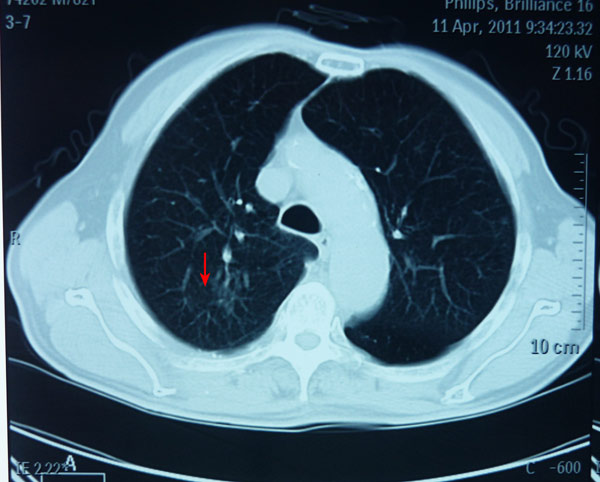

2011年1月17日,老人住进我院肿瘤科。经专家会诊认为老人年纪大,采用目前全球非常先进的立体放射治疗设备——射波刀(不麻醉、不开刀、不出血、不疼痛、精确消灭肿瘤)治疗,每天治疗40分钟,连续3天治疗结束,前后住院6天出院。出院后老人没有特别不适,在家里还下地种菜,做家务等。治疗1年后老人回院复查CT显示肺部癌肿消失。2013年底又再次行CT检查,提示肿瘤无复发。

射波刀治疗后一年肿块消失